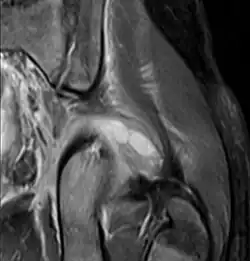

Axial T1 weighted fat suppressed post IV gadolinium contrast enhanced MRI image showing a mutliloculated bacterial abscess in the left gluteal muscle which grew Staphylococcus aureus (methicillin sensitive) thought to be due to tropical pyomyositis.

Coronal fat suppressed post contrast image showing a multiloculated bacterial abscess in the left gluteus minimus muscle due to tropical pyomyositis.